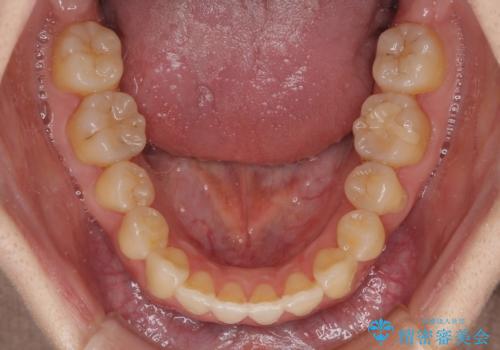

ハーフリンガル 反対咬合の改善

下顎左右の奥にアンカーボルトを使用して、無理のない範囲で後方に移動させ、きれいに仕上げることができました。